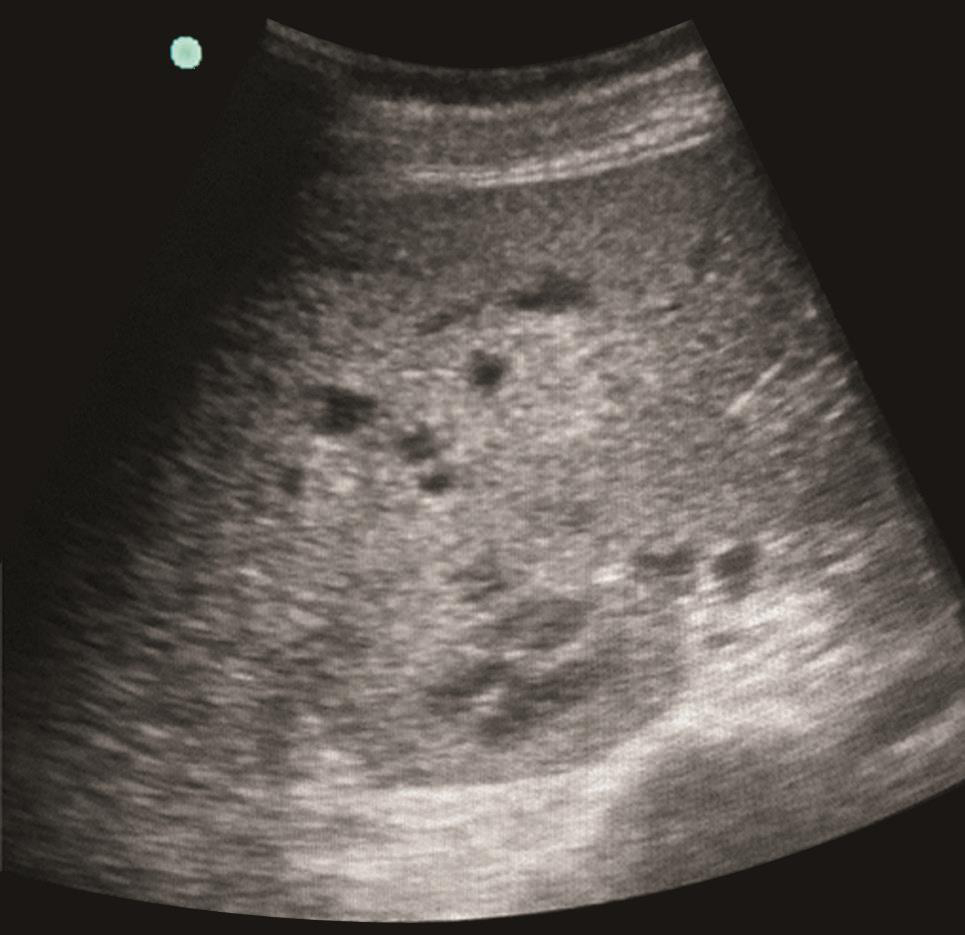

(5)肝脏超声

肝内可见多发低回声区,大小不一,最大约12mm×10mm,界清,扁椭圆形,无包膜,内回声不均,周边及内部未见明显血流信号(图3)。

图3肝脏超声(治疗前)

患者入院后,予亚胺培南/西司他丁(1g,每8小时1次)抗感染治疗,辅以磷酸肌酸钠改善心肌代谢,并继续给予抑制胃酸、保护胃肠黏膜、营养支持(滋养型肠内营养联合静脉营养)、调节肠道微生态、保肝等治疗。床旁腹部超声检查发现中等量腹水,置管引流出淡黄色微浑液体1800ml。腹水常规:白细胞计数2548×109/L,多核细胞76%。入院第4日,鉴于患者腹痛无缓解,且有发热(体温达38.5℃),复查CRP 75.1mg/L,外周血WBC 13.1×109/L,N% 83.0%,不排除合并肠道革兰阳性球菌感染可能,遂加用利奈唑胺(600mg,每12小时1次)加强抗感染治疗。治疗1周后复查,血常规:WBC 9.8×109/L,N% 78.0%,Hb 85g/L,PLT 178×109/L;PCT降至0.82ng/ml;CRP 29.0mg/L;腹水逐渐减少,腹水白细胞计数降至803×106/L;肝、肾功能正常。但患者仍有发热(37.5~38.5℃),无畏寒、寒战,上腹痛无缓解且进行性加重。复查肝脏超声见多发低回声病灶较前增大(图4)。考虑患者WBC、CRP、PCT等全身炎症反应指标改善与感染性腹水引流后全身炎症反应有所下降有关,但腹痛、发热无改善,需考虑肝脏病灶可能为细菌、真菌混合感染,遂加用米卡芬净(150mg,每天1次)经验性抗真菌治疗,并继续超声动态监测肝脏病灶变化(如有液化,可考虑穿刺引流培养以明确病原学诊断)。虽然血液及腹水肿瘤标志物检测没有阳性发现,但仍不能排除肿瘤引起的腹痛及发热,可待肾功能恢复后,择期行腹部增强CT协助诊断,必要时可待凝血功能进一步好转后行肝结节活检以明确诊断。

图4肝脏超声(治疗1周)